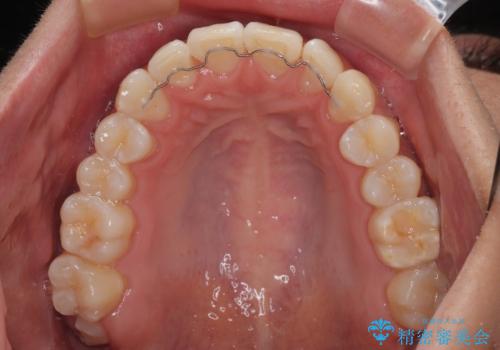

前歯のデコボコをインビザラインで綺麗に改善

- 上下前歯のデコボコとクロスバイトを気にして来院された患者様です。

インビザラインを用い、IPR(歯と歯の間を削る)と歯列全体を拡大させることで、歯並びを整えていくこととしました。

毎日22時間の装着時間を徹底してくださったのですが、左右ともに臼歯が咬合しなくなるという、インビザライン独特の症状が強く長く続いてしまい、終了するまでに長期間を要してしまいました。